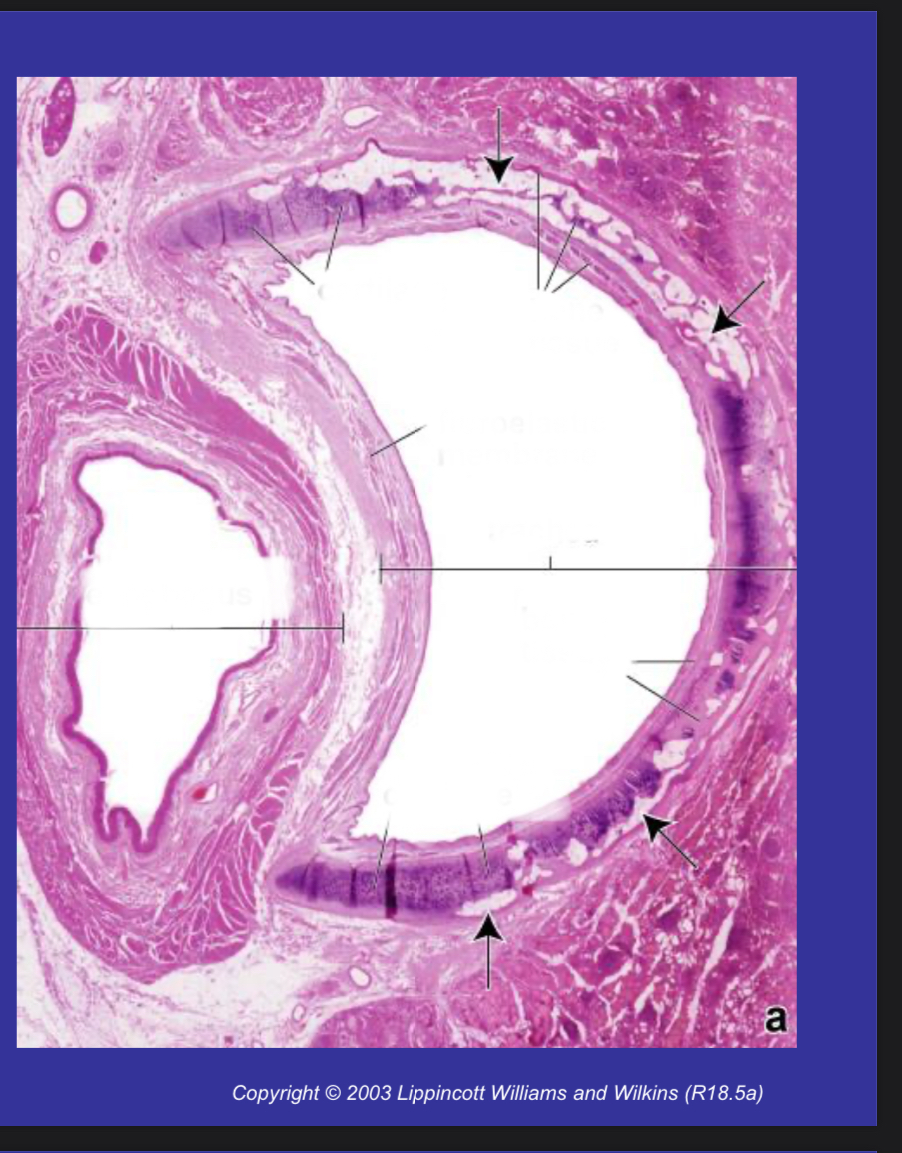

What is seen in the image?

Transverse section of TRACHEA and oesophagus, from an elderly person. The fibroelastic membrane contains the trachealis muscle The C-shaped cartilaginous tracheal ring has been transformed, in part, to bone, a process that occurs with ageing